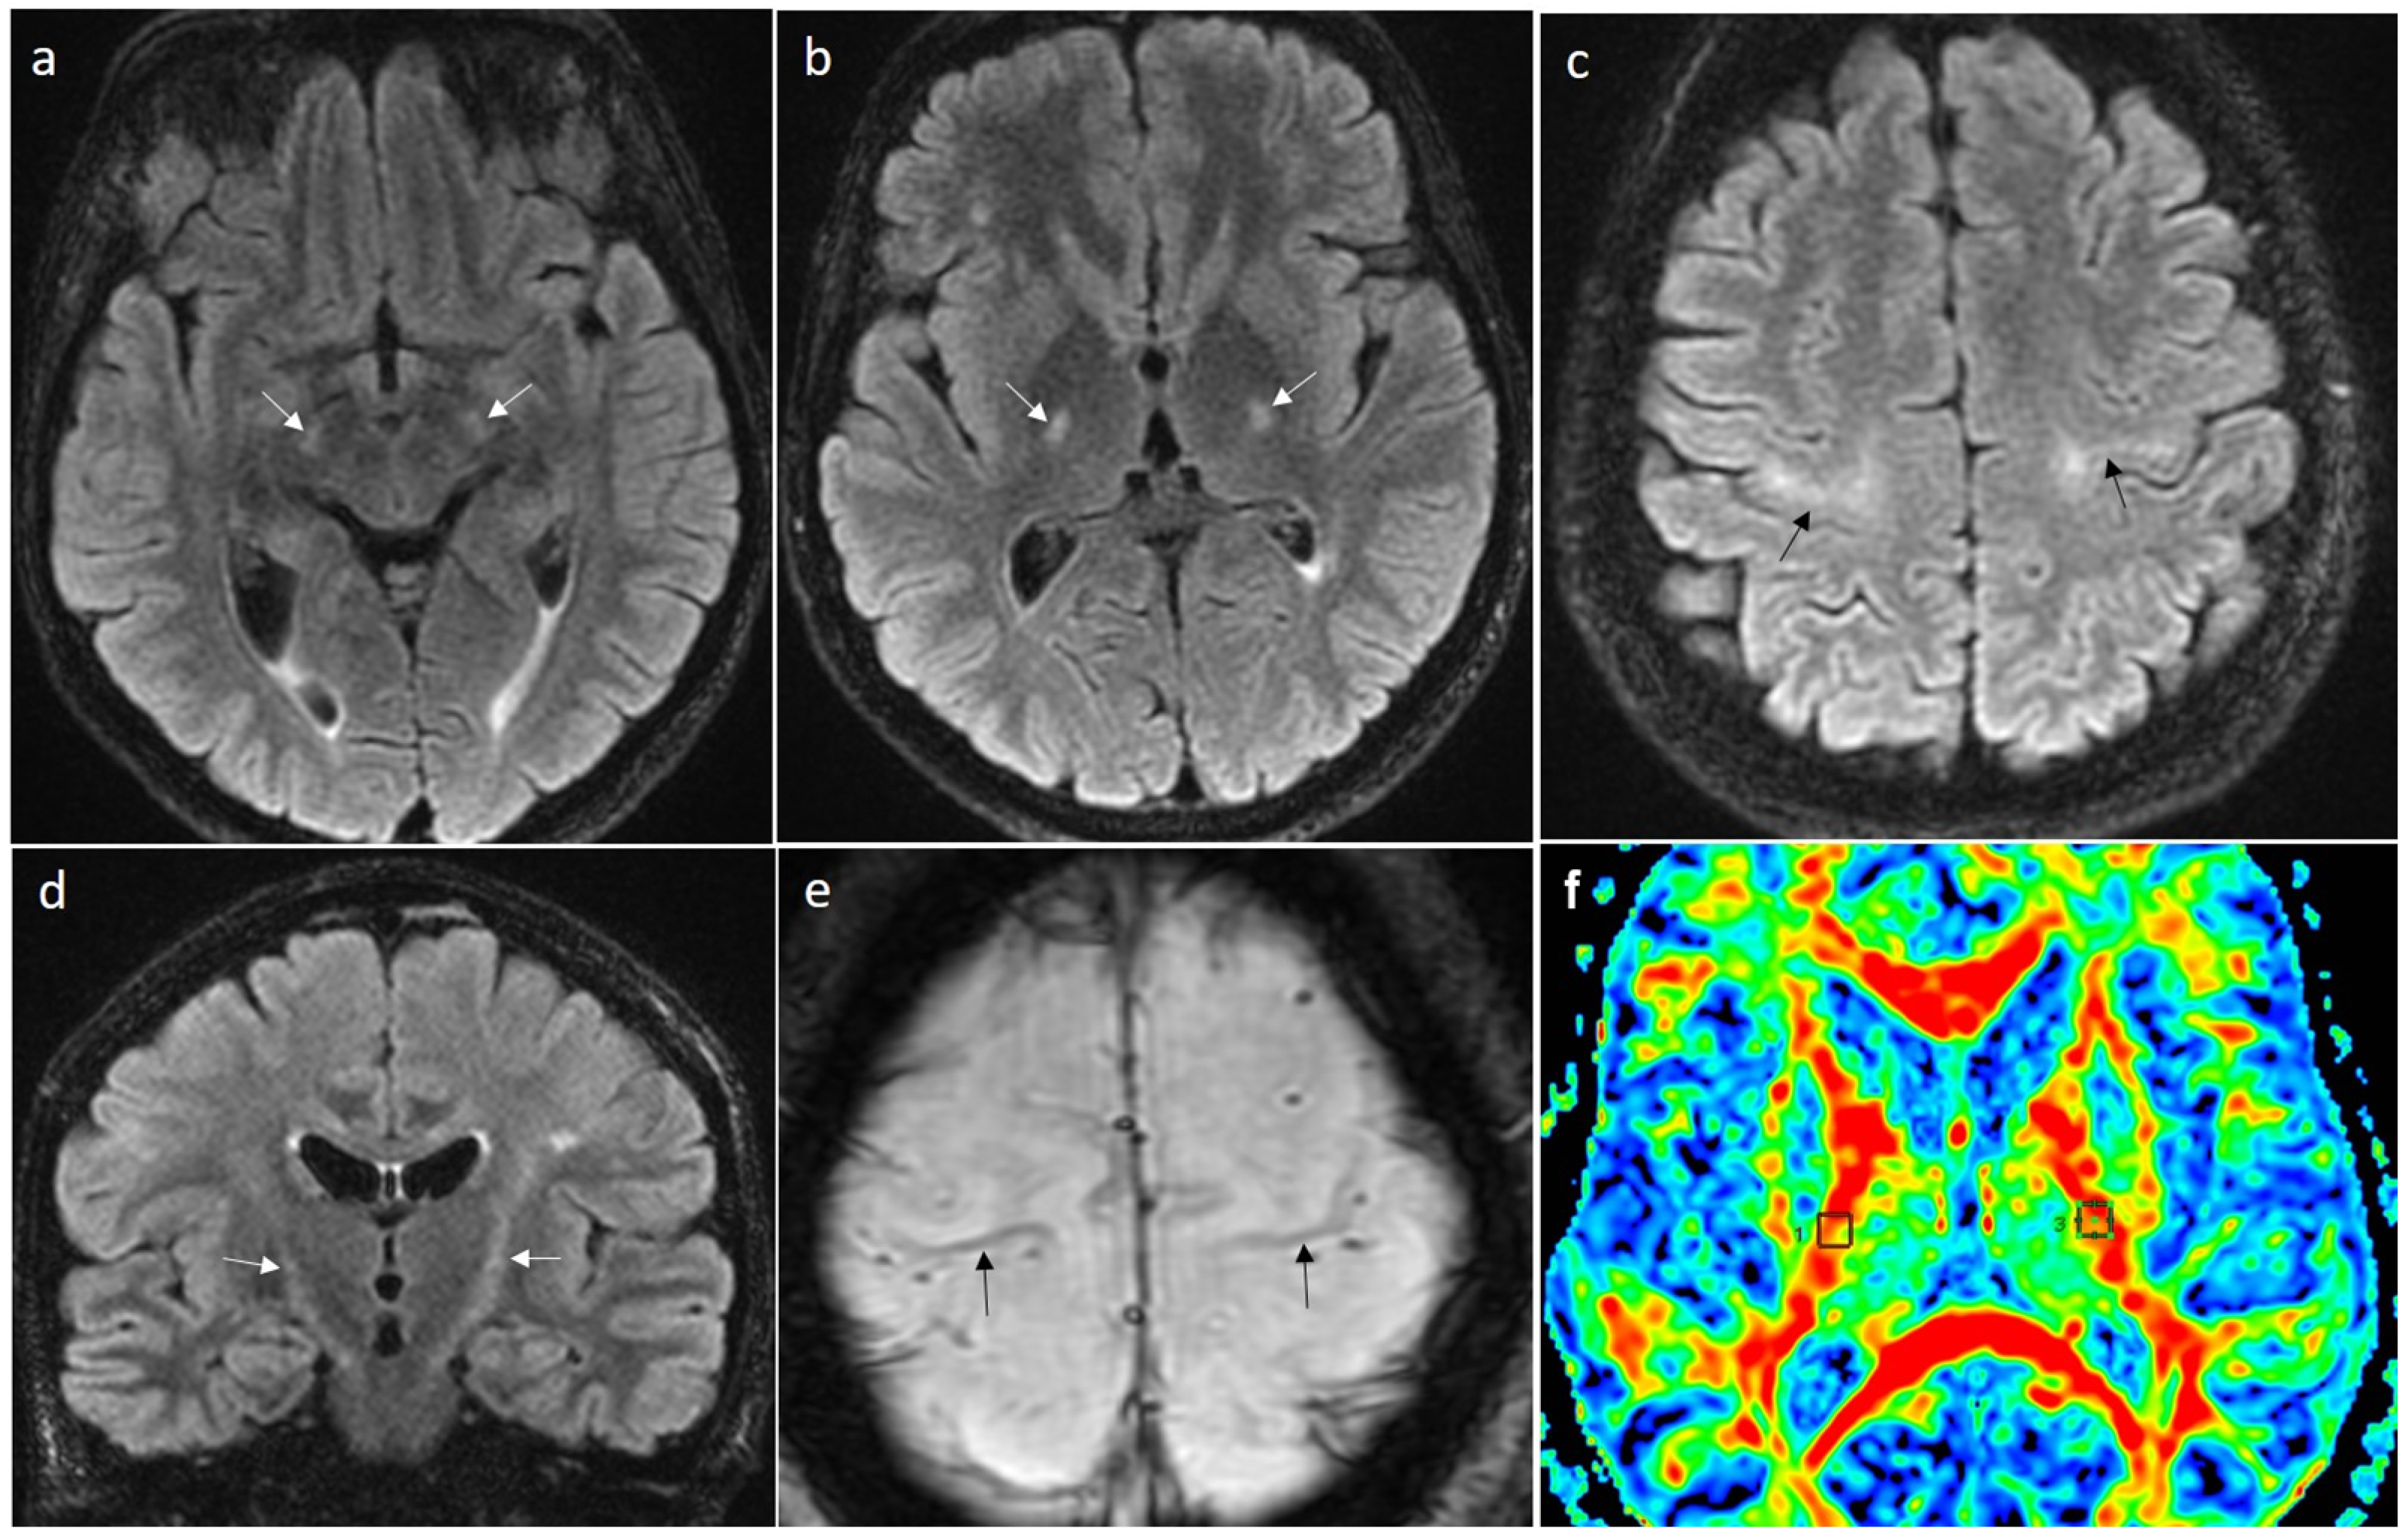

- Cheung, G.; Gawel, M.J.; Cooper, P.W.; Farb, R.I.; Ang, L.C.; Gawal, M.J. Amyotrophic lateral sclerosis: Correlation of clinical and MR imaging findings. Radiology 1995, 194, 263–270, Erratum in Radiology 1995, 196, 800. [Google Scholar] [CrossRef]

- Chakraborty, S.; Gupta, A.; Nguyen, T.; Bourque, P. The “Motor Band Sign:“ Susceptibility-Weighted Imaging in Amyotrophic Lateral Sclerosis. Can. J. Neurol. Sci. 2015, 42, 260–263. [Google Scholar] [CrossRef] [PubMed]

- Desai, A.B.; Agarwal, A.; Mohamed, A.S.; Mohamed, K.H.; Middlebrooks, E.H.; Bhatt, A.A.; Gupta, V.; Kumar, N.; Sechi, E.; Flanagan, E.P.; et al. Motor Neuron Diseases and Central Nervous System Tractopathies: Clinical-Radiologic Correlation and Diagnostic Approach. Radiographics 2025, 45, e240067. [Google Scholar] [CrossRef]

- Maj, E.; Jamroży, M.; Bielecki, M.; Bartoszek, M.; Gołębiowski, M.; Wojtaszek, M.; Kuźma-Kozakiewicz, M. Role of DTI-MRI parameters in diagnosis of ALS: Useful biomarkers for daily practice? Tertiary centre experience and literature review. Neurol. Neurochir. Pol. 2022, 56, 490–498. [Google Scholar] [CrossRef] [PubMed]